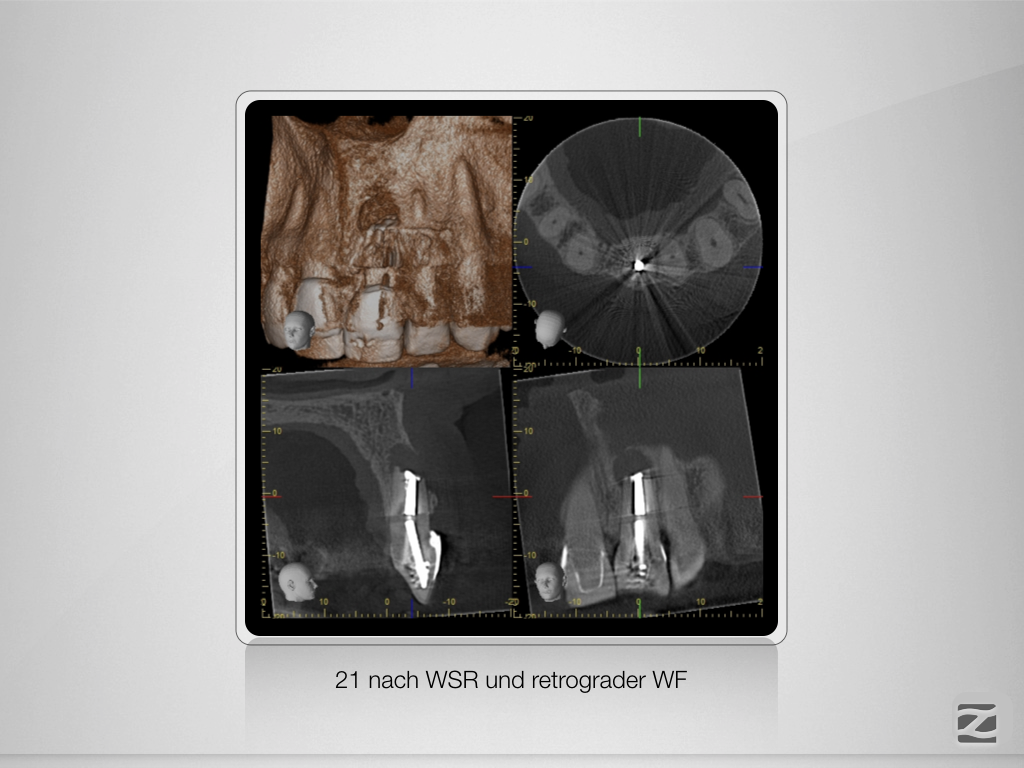

Hürdenlauf – Revision nach Resektion